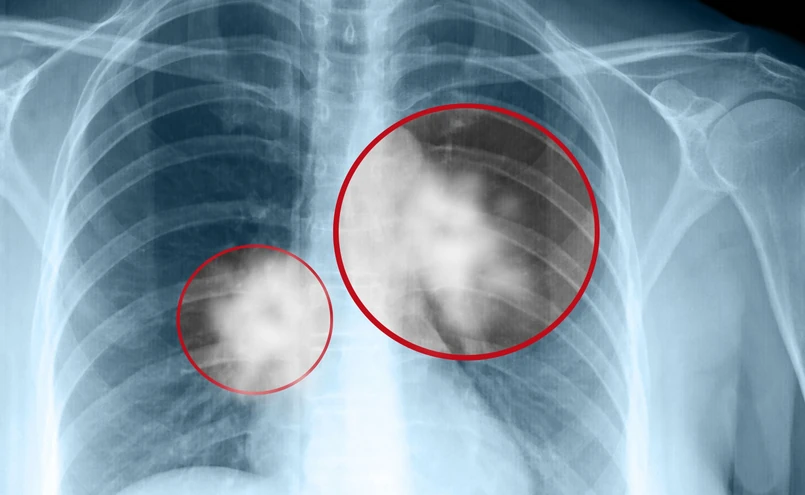

Po pierwsze, są to opóźnienia w diagnostyce wstępnej, kiedy to pacjent czeka na wizytę w poradni ambulatoryjnej lub na badania obrazowe. - Karta DILO przez kilka lat funkcjonowała bardzo dobrze, ale teraz niestety motywacja lekarzy POZ do kierowania chorych na szybką diagnostykę trochę spadła i tych chorych w poradni, chociażby w poradni przyszpitalnej Instytutu Gruźlicy i Chorób Płuc, jest mniej niż jeszcze kilka lat temu - podkreślał dr Mateusz Polaczek. Kiedy chory trafi w końcu do pulmonologa lub chirurga, to często mamy już do czynienia z rozsianym nowotworem.

Od stycznia br. weszły zmiany mające na celu przyspieszenie wstępnej diagnostyki - lekarze rodzinni mają prawo wystawić skierowanie na tomografię komputerową klatki piersiowej, jednak nadal wiedza na ten temat nie jest powszechna. - Jeśli pacjent do pulmonologa czy torakochirurga trafi już z wynikiem takiego badania, to zdecydowanie o kilka tygodni przyspieszy całą ścieżkę diagnostyczną - dodał dr Polaczek.